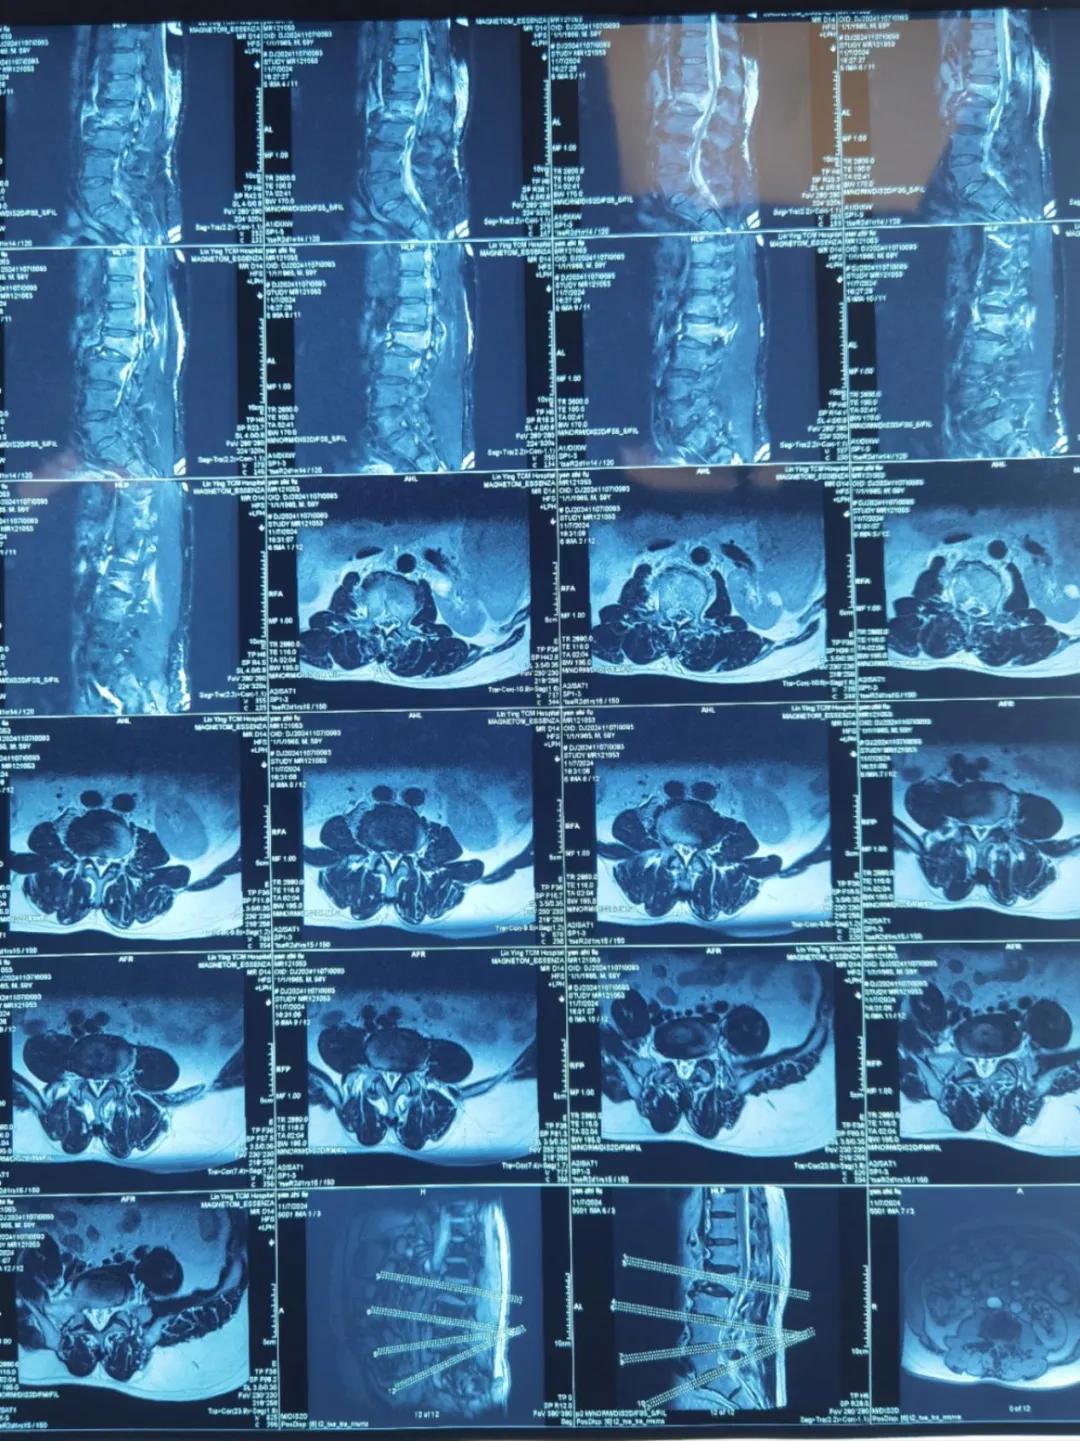

“醫(yī)生,這是之前的檢查結果,還需要再做檢查嗎?”閆大叔從外院轉來被推進智能微創(chuàng)骨科。幾天前,他在老家的中醫(yī)院進行了抽血檢驗和磁共振檢查,因為腰疼嚴重、行動不便檢查過程也十分不易。

智能微創(chuàng)骨科副主任李鵬認真檢查了閆大叔帶來的片子,還有電腦系統(tǒng)上彈出來的檢驗結果。外院的核磁和X線可以清楚的看到情況已經(jīng)比較嚴重,需要盡快手術。沒有二次檢查,不僅節(jié)省患者就醫(yī)費用,還使就醫(yī)更高效、便捷直接入院接受治療。閆大叔懸著的心放了下來,其他醫(yī)院的片子能直接用,檢查在家附近的醫(yī)院做,手術在漯河市骨科醫(yī)院做,便捷的結果'互認'讓他直夸“真方便!咱老百姓更省心、更放心了!”